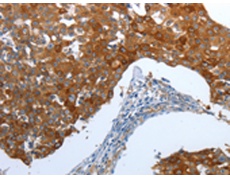

中文名稱:兔抗CEACAM5多克隆抗體

Anti-CEACAM5 rabbit polyclonal antibody

別      名: CEA, CD66e

Members of the CEACAM subfamily, including CEACAM5, belong to the CEA gene family. For general information on the CEA gene family, see CEACAM1. Cell surface glycoprotein that plays a role in cell adhesion and in intracellular signaling. Receptor for E.coli Dr adhesins. Found in adenocarcinomas of endodermally derived digestive system epithelium and fetal colon.

ELISA, IHC

CEACAM5

Synthetic peptide of human CEACAM5

Carcinoembryonic antigen-related cell adhesion molecule 5

CEA, CD66e

P06731

ELISA Recommended dilution:

1000-5000

IHC positive control:

Human breast cancer and Human thyroid cancer

IHC Recommend dilution:

25-100